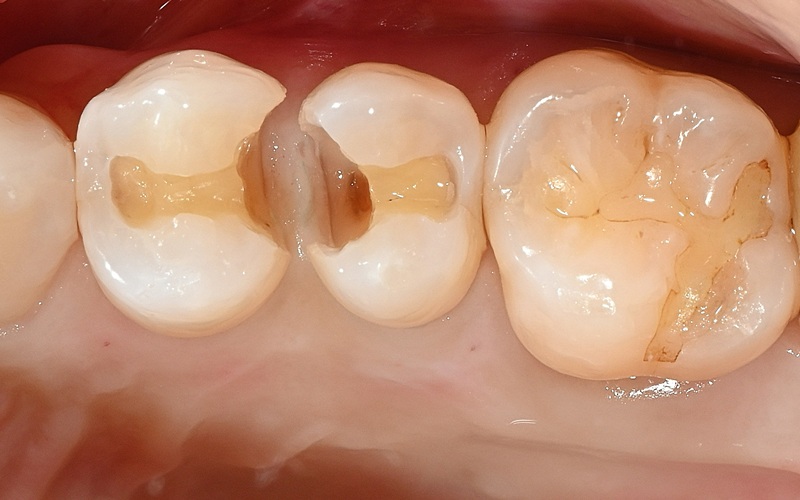

Case4

術前

術中

術後

| 治療名 | ダイレクトボンディング・セラミックインレー |

|---|---|

| 治療説明 | 以前他院で行ったハイブリッドセラミックインレーが劣化したためセラミックインレーとダイレクトボンディングで再修復を行いました。 |

| 治療回数・期間 | 2回 |

| 副作用とリスク | 一時的に知覚過敏が生じることがあります。セラミックとレジンが破折し、再修復が必要になる可能性があります。 |

| 料金(税込) | セラミックインレー:77,000円 ダイレクトボンディング:55,000円 合計:132,000円 |